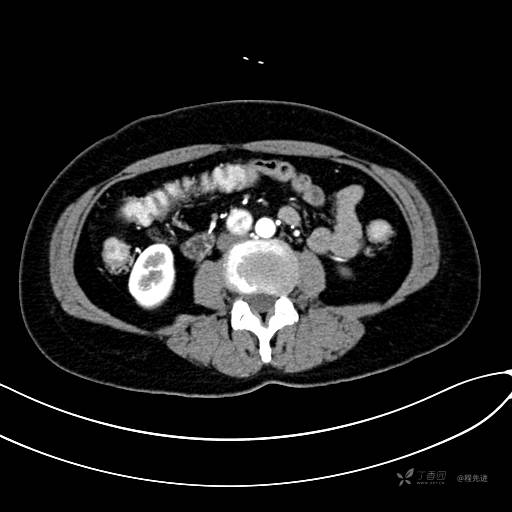

CT增强静脉期